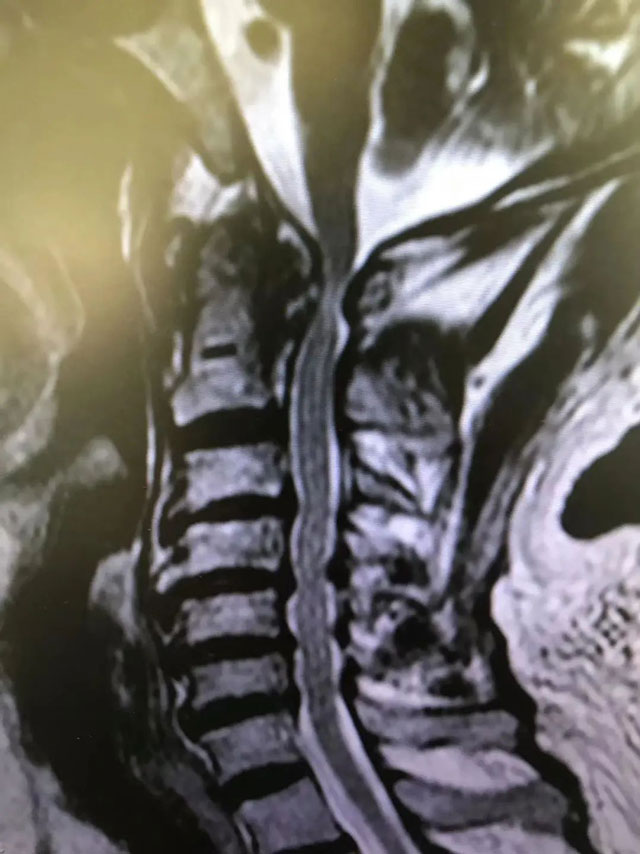

在生命中枢“动刀”挽救患者 西南医大附院脊柱外科王清教授团队完成罕见手术!

一周前,在西南医科大学附属医院脊柱外科王清教授的带领下,医院首例也是脊柱外科界难度系数较高的手术——颈后方寰枢椎侧方入路脊髓前方肿瘤切除脊髓解压术和枕颈固定术顺利完成。“患者在重症监护病房,正处于术后观察阶段。”10月20日,王清告诉记者,...